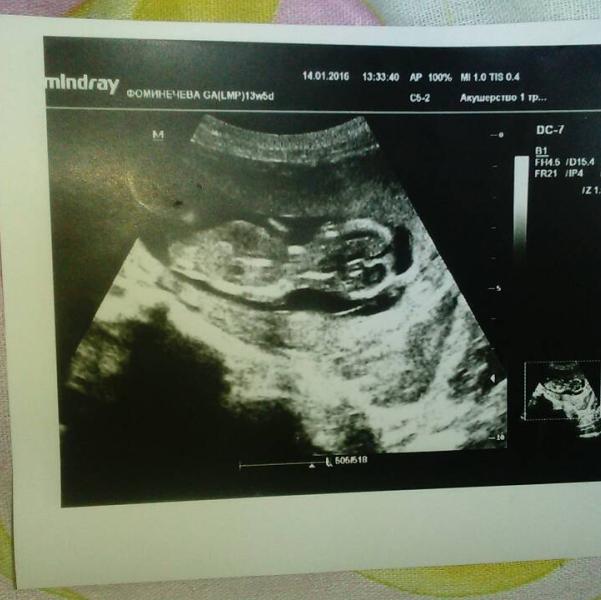

сказали что будет девочка, ура ура, дай бог что бы все хорошо было,тьфу тьфу

50 на 50, но больше всего на девочку похожа сказала, почему то и мне кажется что девочка